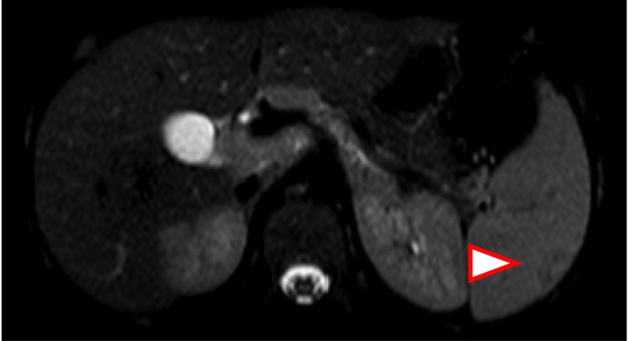

con brivido e dolore al fianco sinistro. L'ecografia addominale

(Figura 1) evidenzia �all'ilo

epatico linfonodi ingranditi e nella

milza alcune aree sfumatamente ipoecogene da possibili

localizzazioni linfomatose.� Figura 1. L�ECO

addominale evidenzia nella milza alcune aree sfumatamente ipoecogene